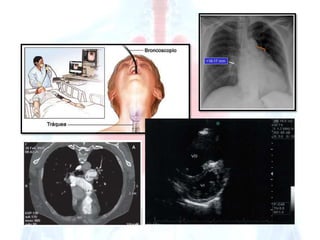

Exámenes

complementa

rios

Radiografía de

tórax

E.C.

Tomografía

computarizada

helicoidal con

contraste

Electrocardiogram

Estudios

hemodinámicos

a Ecocardiograma

Exámenes complementa rios Radiografía de tórax E.C. Tomografía computarizada helicoidal con contraste Electrocardiogram Estudios hemodinámicos a Ecocardiograma